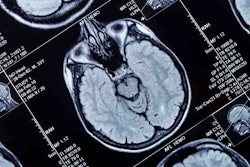

Racial and ethnic minority groups in the U.S. are inadequately represented in Alzheimer's neuroimaging research, according to a study published July 25 in Communications Medicine.

Racial and ethnic minorities in the U.S. carry disproportionate Alzheimer's disease burden compared to their White counterparts. It doesn't help that they are often underrepresented in Alzheimer's disease neuroimaging research -- a fact that affects the generalizability of trial findings, biomarker cutoffs, and treatment effects, Han and colleagues noted.

Across the articles, participants were 84% to 87% white -- a group that makes up less than 60% of the U.S. population -- and all racial and ethnic minority groups (Black/African American, Hispanic/Latino, Asian American and American Indian/Alaska Native) were underrepresented, the investigators found.